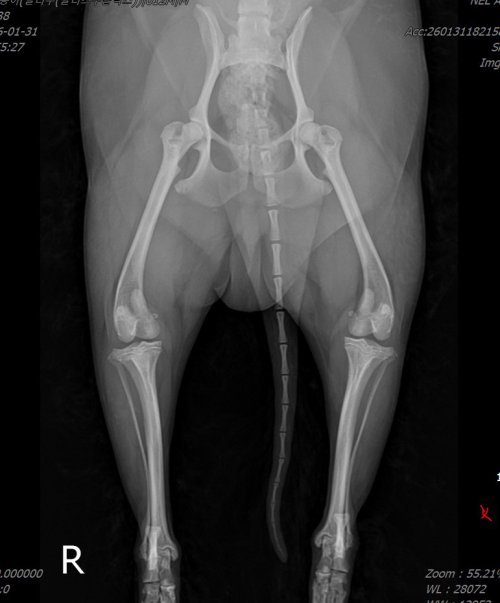

잘못된 예시: 무릎뼈(슬개골)와 허벅지뼈가 안쪽으로 돌아가 있어 정확한 각도 측정이 불가능